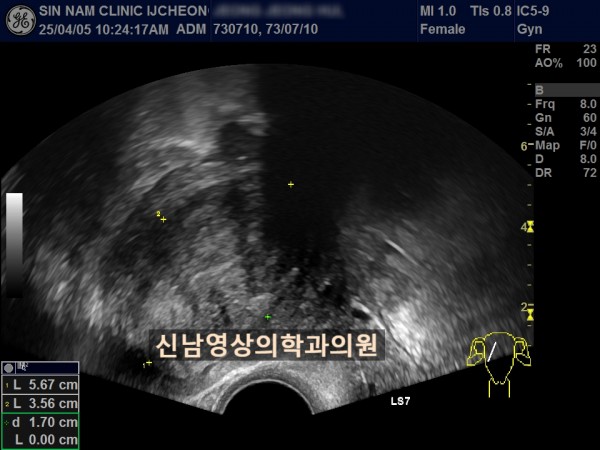

연령 : 52세

하복부 통증으로 내원하셨고, 초음파 검사상 자궁선근종과 난소낭종이 발견되었고, 난소암 혈액검사를 진행했습니다.

난소암 혈액검사 결과는 정상범위로 약간 높은 수치였기에 생리 끝나고, 다시 추적검사를 진행하기로 했지만 복통이 심해져 수술 진행했고, 수술장에서는 암의 가능성이 없는 것으로 전달 받았으나 최종 조직검사상 난소암으로 진단되었습니다.

여성들의 경우 난소 내막종에서 난소암으로 진행될 위험이 있고, 자궁선근종이 있는 분들은 난소내막종이 동반될 가능성도 높기 때문에 주기적으로 추적검사가 필요하고, 난소암 혈액검사와 초음파상 혹의 모양을 종합적으로 판단해 수술결정을 하게 됩니다.